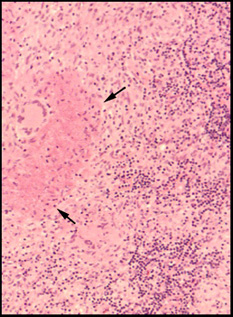

These young granulomas (arrows) in the skin have no surrounding rim of mononuclear cells and are called naked granulomas. |